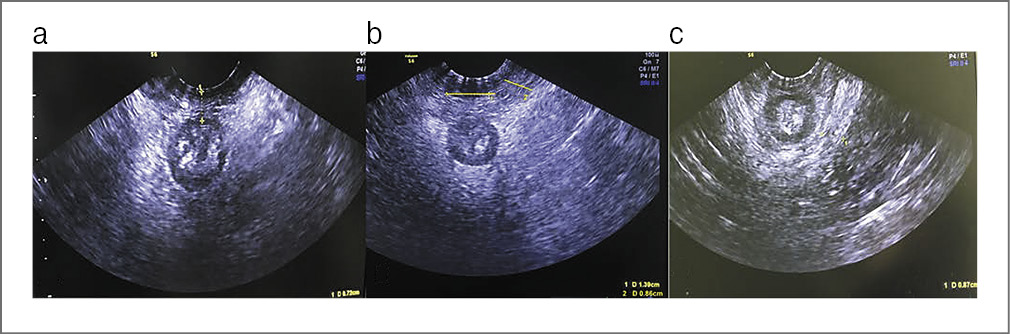

Заключение: сонографические признаки недостаточности мышц ТД (рис. 1), цистоцеле с правосторонним паравагинальным и центральным дефектом фасции (рис. 2), полный правосторонний отрыв m. levatоr ani (рис. 3).

Рис. 1. Несостоятельность мышц ТД: a – уменьшение высоты сухожильного центра (D=0,52 cм); b – диастаз и истончение m. bulbocavernosus (D=1,49 cм и D=0,56 cм); c – истончение m. puborectalis (D=0,51 cм).